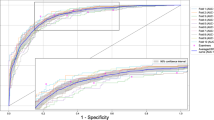

To rapidly determine model performance, the average precision [35] (AP; i.e., the area under the curve) of the implant and marginal bone loss lesion areas, as well as the mean average precision (mAP) of an intersection over unit (IoU) of > 0.5, were calculated using the following equation:

where Areapred and Areagt represent the predicted area of the bounding box and the ground truth bounding box, respectively. The IoU threshold was set at 0.5 because this value is commonly used in studies of object detection [36]. The mAP was calculated by determining the mean AP across all classes. Higher values indicated better learning system performance.

The AP for implants approached 0.99 after 10,000 iterations (Fig. 2a), indicating that the implants could be detected with high accuracy. The AP for marginal bone loss gradually increased with an increasing number of iterations. When the number of iterations reached 30,000, the AP value fluctuated slightly; it eventually stabilised at 0.47 after 60,000 iterations (Fig. 2b). The mAP of implants and marginal bone loss was 0.73 (Fig. 2c).

The average precision [35] (AP; i.e., the area under the curve) of the implant and marginal bone loss lesion areas, as well as the mean average precision (mAP) of an intersection over unit (IoU) of > 0.5, were calculated. a average precision of implant classification; b average precision of marginal bone loss lesion classification; c mean average precision